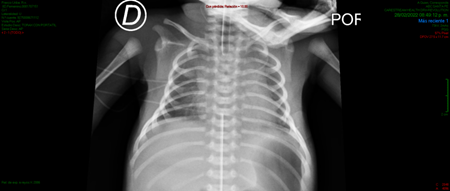

The mother came into the tocosurgical unit because of fetal tachycardia detection, and the interruption of pregnancy by c-section was indicated. A male newborn was obtained without muscle tone. He required orotracheal intubation during neonatal resuscitation because of apnea that didn´t resolve with positive pressure ventilation. He obtained an Apgar score of 3/7 and was admitted to the Neonatal Intensive Care Unit (NICU) with the suspicion of TNMG. At the physical examination, he was hypoactive, had generalized hypotonia, no spontaneous respiratory effort, muscle strength in the four extremities of 2/5 and hypotrophy of the shoulder girdle. He had positive deep tendon reflexes, no clonus. Thorax x-ray revealed a bell chest image (Figure 1).

Figure 1 Thorax X-Ray revealing a bell-chest image, in a patient with Transient Neonatal Myasthienia Gravis (TNMG).